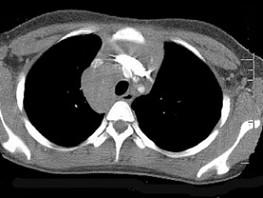

[单选题]7岁,男,发热、消瘦,数月前触及颈部淋巴结肿大,CT和MR检查如图,请选择最可能的诊断()A.淋巴瘤B.结节病C.淋巴结核D.转移性淋巴肿大E.胸腺瘤

[单选题]女,32岁,发热、消瘦,数月前触及颈部淋巴结肿大,CT和MR检查如图,最可能的诊断是()A .淋巴瘤B .结节病C .淋巴结核D .转移性淋巴肿大E .胸腺瘤